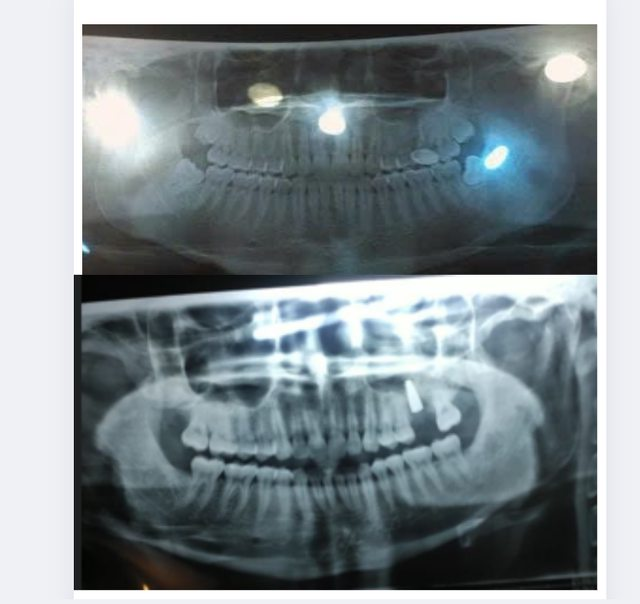

This is a female case

Photo 1 (before extraction), Photo 2 (after extraction)

As you can see in the red circle, the lower right jaw bone that was extracted is concave instead of flat, both upper jaw 8 tooth sockets are also black and empty

The reason is contrary to the logic as in case 1 I analyzed, the jaw structure of this case has enough position for all 4 wisdom teeth, all 4 grow beautifully but still extracted -> causing gradual bone loss over time is certain because the 8th tooth participates in the chewing function and creates mechanical chewing force to maintain the jaw bone structure